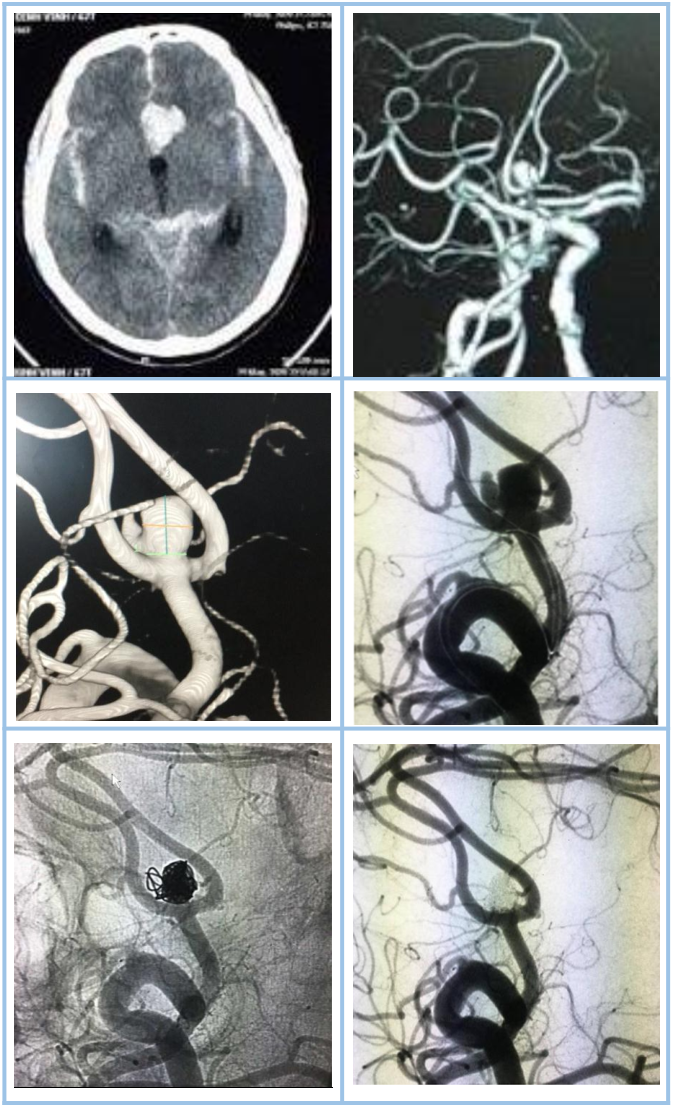

Thông động-tĩnh mạch não (AVM)

Thái độ xử trí đối với dị dạng thông động-tĩnh mạch não đã được hiệp hội Tim mạch và đột quỵ Hoa Kỳ đưa ra vào năm 2017. Nút mạch đối với dị dạng AVM có xuất huyết não cấp thường đặt ra để điều trị chảy máu do phình mạch cạnh ổ nidus dị dạng hoặc nút tắc chọn lọc điểm chảy máu giảm nguy cơ chảy máu tái phát. Sau giai đoạn cấp khi mà khối máu tụ đã tiêu hết (khoảng 4-6 tuần), thì việc nút mạch điều trị dị dạng AVM tùy thuộc vào mục tiêu cụ thể cho từng bệnh nhân bao gồm nút mạch triệt để dị dạng (qua đường động mạch hoặc tĩnh mạch), nút mạch giảm một phần thể tích nidus trước mổ giúp giảm nguy cơ phẫu thuật hoặc nút mạch một phần dị dạng phối hợp với xạ phẫu.